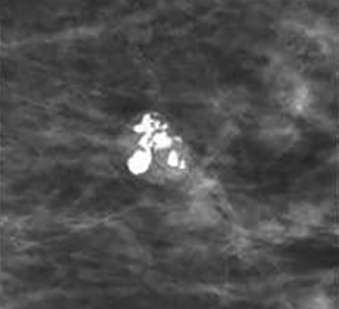

Coarse or popcorn-like calcifications

Coarse or popcorn-like calcifications: dense calcifications larger than 2-3 mm, often coalescing over time and indicative of hyalinizing fibroadenoma